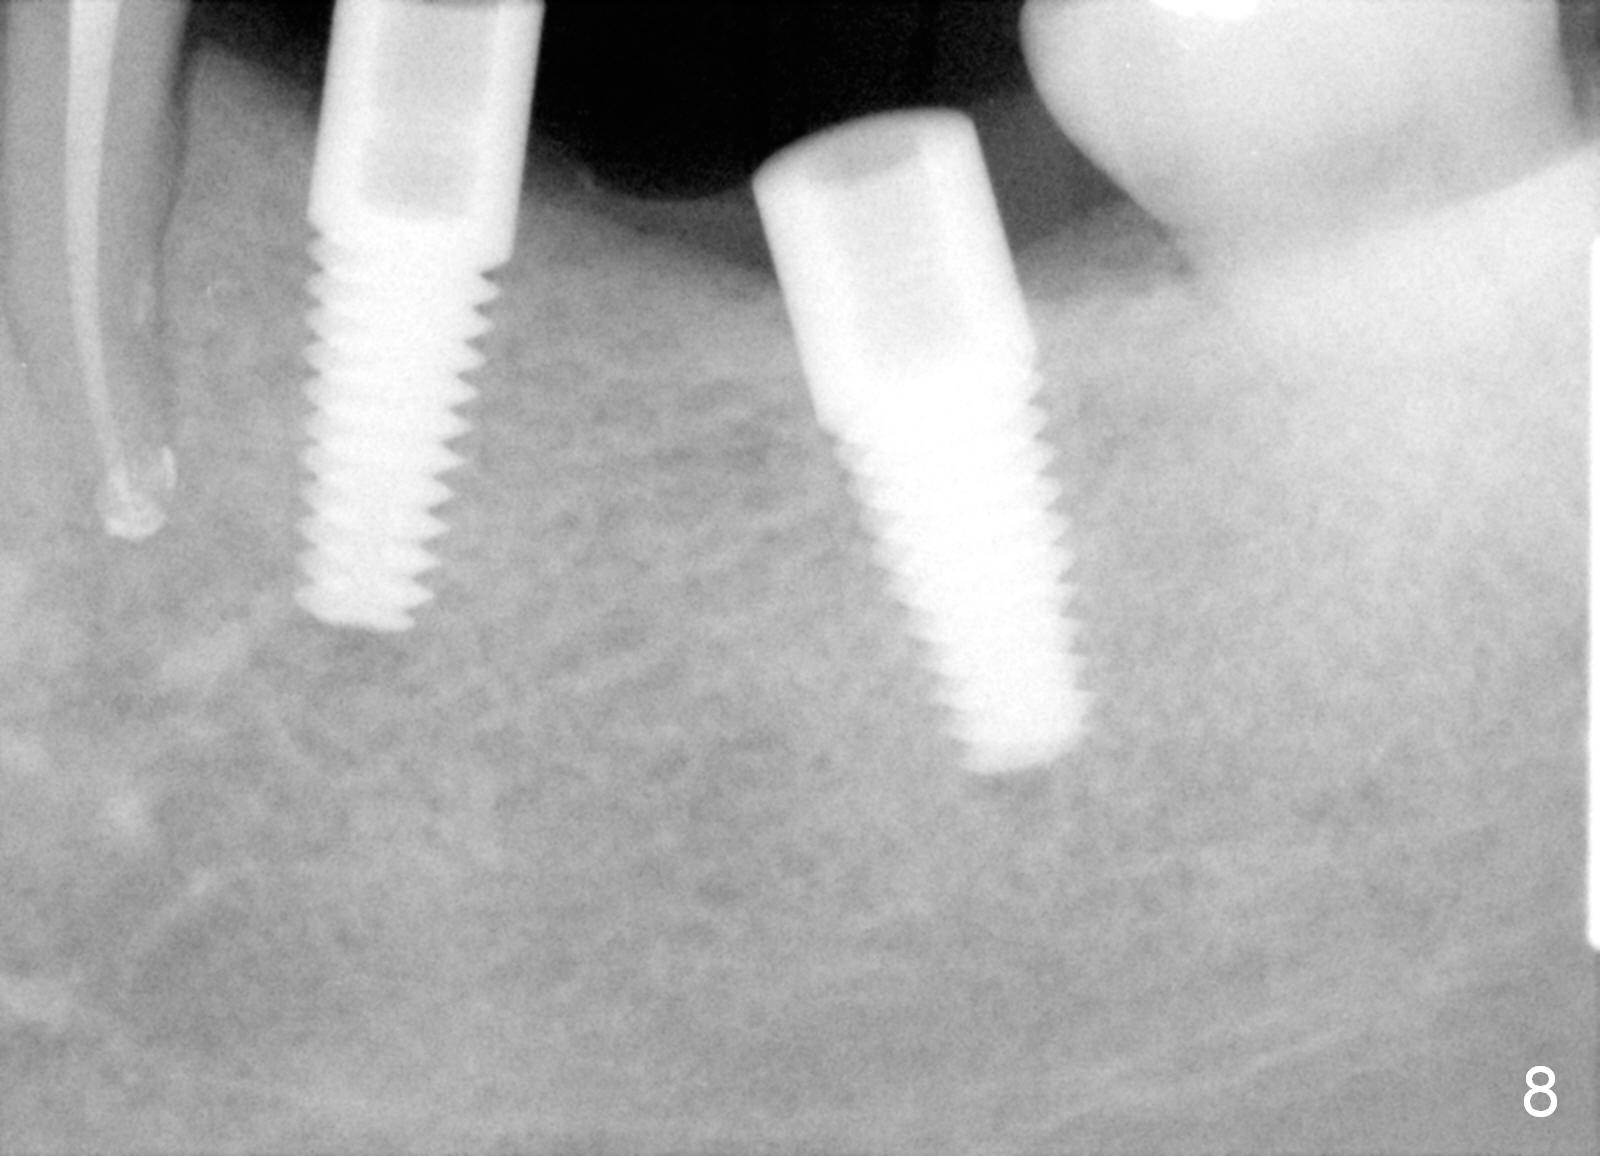

One year 2 months post root canal therapy at #20 (Fig.4), osteotomies are initiated at #18 and 19. The trajectory at #19 is subsequently corrected (Fig.5); that of #18 should be also corrected (arrow). The fact of the narrow ridge (Fig.6) is also ignored intraop. Without further adjustment, the osteotomies are enlarged (Fig.7) and the implants are placed (Fig.8: 4.5x14, 5x14 mm). As expected, the buccal coronal implant surface is exposed. The buccal plate is decorticated with placement of autogenous bone graft. Periodontal dressing is applied. Postop, the wound is infected with wound gapping. With irrigation, the wound finally heals.